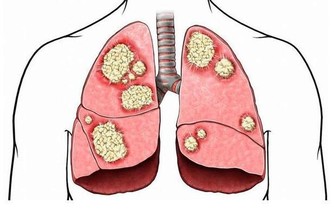

糖耐量異常就是指人體對葡萄糖的耐受能力出現了異常,人體分泌的胰島素對處理葡萄糖的能力,不如正常人迅速有效。這種異常通常能反應在血糖值上,即人體在進食2小時後,血糖超過正常的7.8mmol/L,但仍未達到11.1mmol/L,或者空腹血糖在6.2 mmol/L 至7 mmol/L 之間,這種叫做空腹葡萄糖受損。出現糖耐量異常的人處於正常人向糖尿病過渡的階段,雖然還沒有成為糖尿病患者,但卻極有可能發展為糖尿病,據統計,每年有5-8%的糖耐量異常患者發展為2型糖尿病。

一旦發展為糖尿病,則不可逆轉,所以這部分人要警惕,

趁糖尿病還未“敲門”,趕緊控制血糖,積極干預。